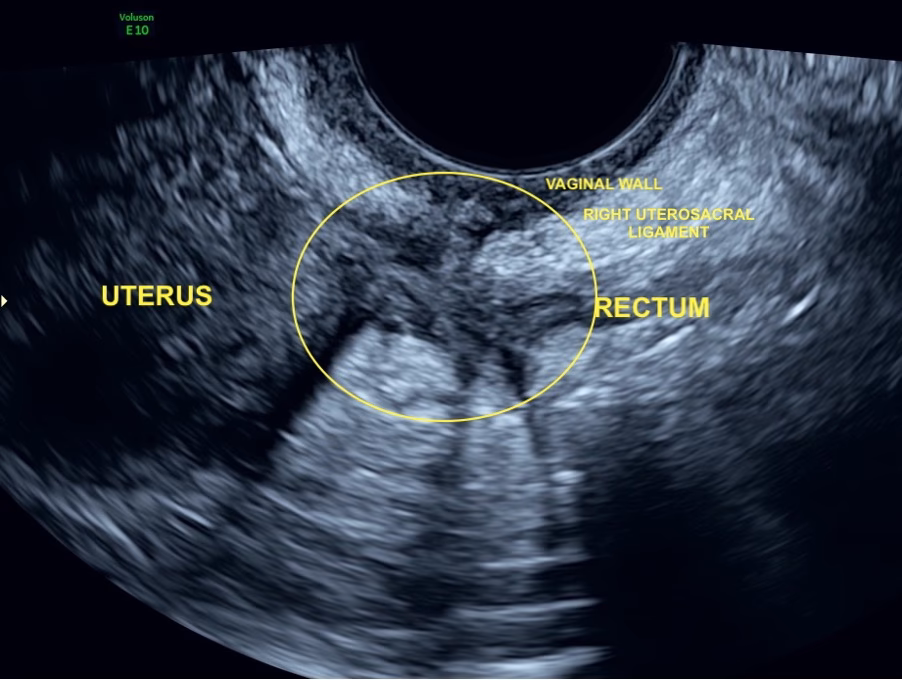

- Dyb Infiltrerende Endometriose (DIE): Dette er den mest alvorlige form, hvor vævet vokser dybt ind i organerne. Det kan findes på blæren, tarmen, bagsiden af livmoderhalsen og de ligamenter, der holder livmoderen på plads. Disse knuder (noduli) kan variere i størrelse fra få millimeter til flere centimeter.

En ultralydsscanning bruger lydbølger til at skabe billeder af kroppens indre organer. Til at undersøge for endometriose anvendes en transvaginal ultralyd, hvor en slank probe føres ind i skeden. Dette giver de klareste og mest detaljerede billeder af bækkenorganerne. Selvom det kan være ubehageligt, især hvis man har smerter, er proceduren sikker og tolereres generelt godt.

- Grundig gennemsøgning: Til sidst undersøges områderne foran og især bag livmoderen minutiøst for at finde de mørke knuder, der kendetegner dyb endometriose.